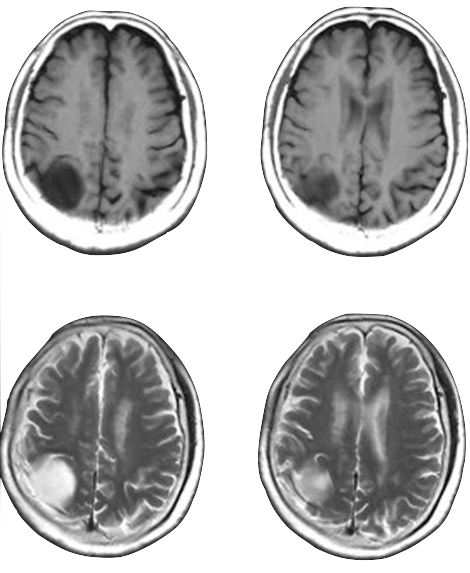

Traditional

3T MRI

AI-Driven

0.055T MRI

MRI source imagery: Liu et al., "A low-cost and shielding-free ultra-low-field brain MRI scanner" (Nat Commun, 2021)